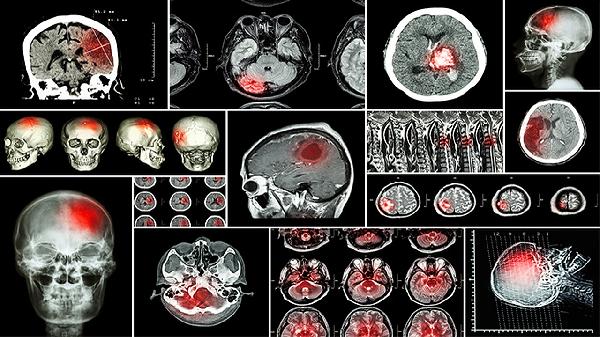

脑供血不足和短暂性脑缺血的主要差异体现在病因、发作时长以及症状表现上。前者多因血管长期病变导致,症状持续时间较长;而后者是由于血管突然被阻塞引起的急性事件,通常在24小时内会完全恢复。

脑供血不足往往与动脉硬化、高血压等慢性疾病有关,血管逐渐变窄,造成血液供应减少。患者可能会出现头晕、记忆力下降、注意力不集中等症状,这些情况容易反复,并且可能逐渐加重。颈椎问题压迫血管或血液过于黏稠也可能成为诱因。这类状况需要通过改善生活习惯、控制原发疾病以及长期服药来管理,例如使用阿托伐他汀钙片或尼莫地平片等药物来延缓病情发展。

短暂性脑缺血是一种突发性的脑血管问题,通常是由于血栓或栓子暂时堵塞血管,之后又自行溶解。常见症状包括一侧肢体无力、说话不清或视力模糊,这些症状一般在几分钟到一小时内消失,最多不超过24小时。虽然症状短暂,但大约有三分之一的患者未来可能会发展成脑梗死。临床上常用阿司匹林肠溶片或氯吡格雷片等药物来预防再次发生,严重情况下可能需要手术干预,如颈动脉内膜剥脱术。